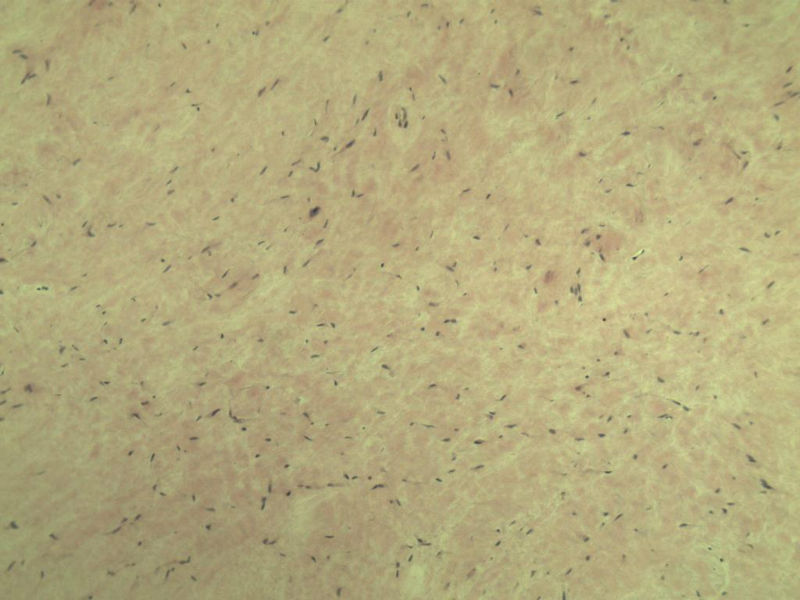

男,51岁, 4月前患者无意中发现右腘窝一包块,约核仁大小无疼痛, 4月来包块进行性生长

灰褐类圆形包块一个,直径 5 cm,切面灰白,实性,编织状。 请各位老师看看 是什么? 谢谢!